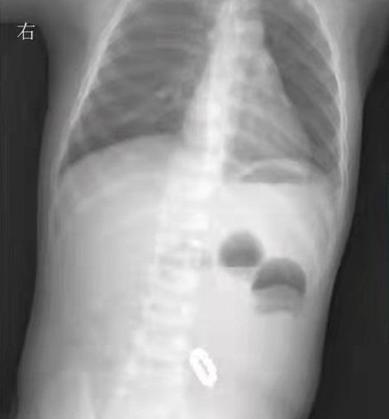

一旦被误吞,轻则会有腹痛呕吐的症状,如果不能随着消化道排出体外,还会造成肠胃穿孔或肠梗阻,甚至危及生命的情况。

因为巴克球具有高磁力,进入到肠道内的小球会互相追赶,互相吸附,导致肠管壁被迫夹压在一起。

随着肠道的不停蠕动,高磁力的小球之间互相摩擦,会将脆弱的肠壁磨出一个个小孔,最终造成肠穿孔、肠堵塞、腹腔感染等后果,甚至危及生命。

2019年,浙江的一个8岁男孩误吞了4颗巴克球,医生检查时发现他的食管下段和胃底紧紧的吸扣在一起,若不是紧急手术取出,这些小磁球差点把食管和胃都压烂了。